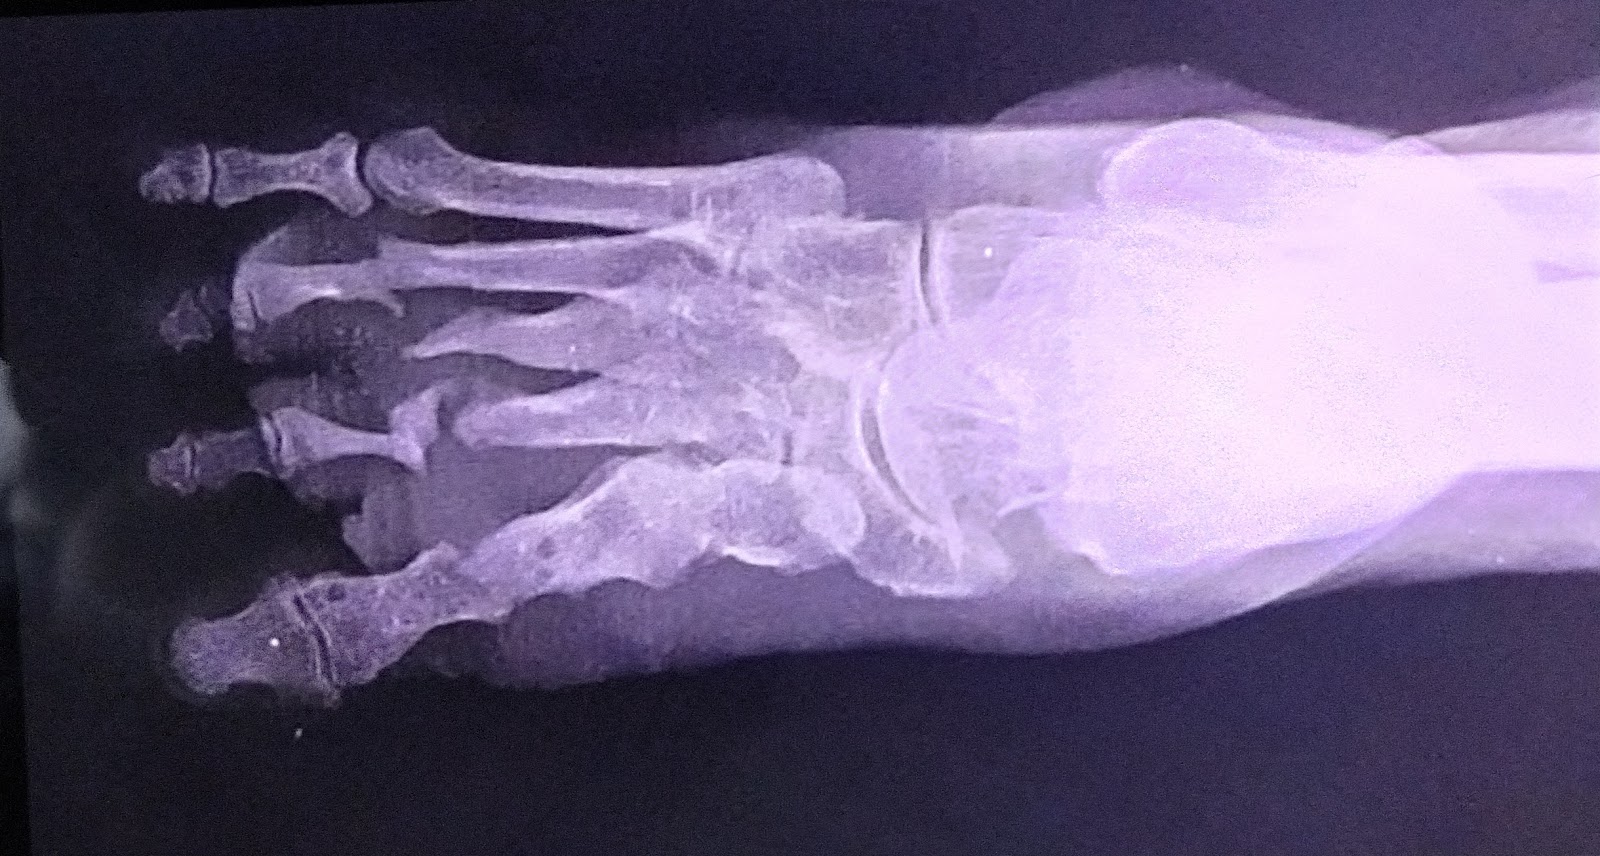

A 670yr old male came with complaints of fever since 2 days and wound on the right foot

Patient was apparently asymptomatic 2 years ago then he had a wound on the right foot it is not healed since 2 years even he visited so many hospitals

The pain in the right foot is flight pain,tingling and numbness present